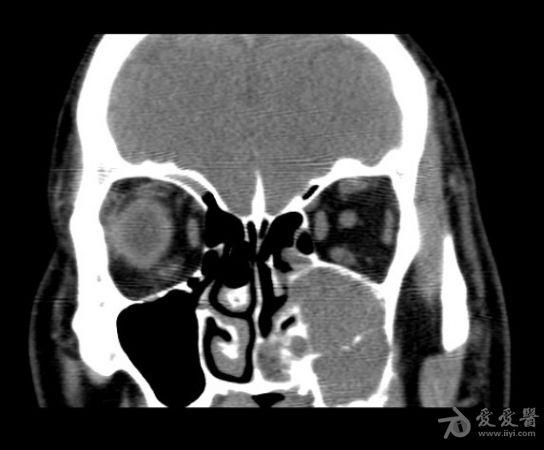

前段時間感覺鼻咽部很不舒服。晚上睡覺還容易打呼嚕。這兩天感覺有些嚴重了。早上起來的時候,鼻咽部感覺特別不舒服。感覺黏黏的。今天我到醫院去看了一下。醫生的態度很不錯...